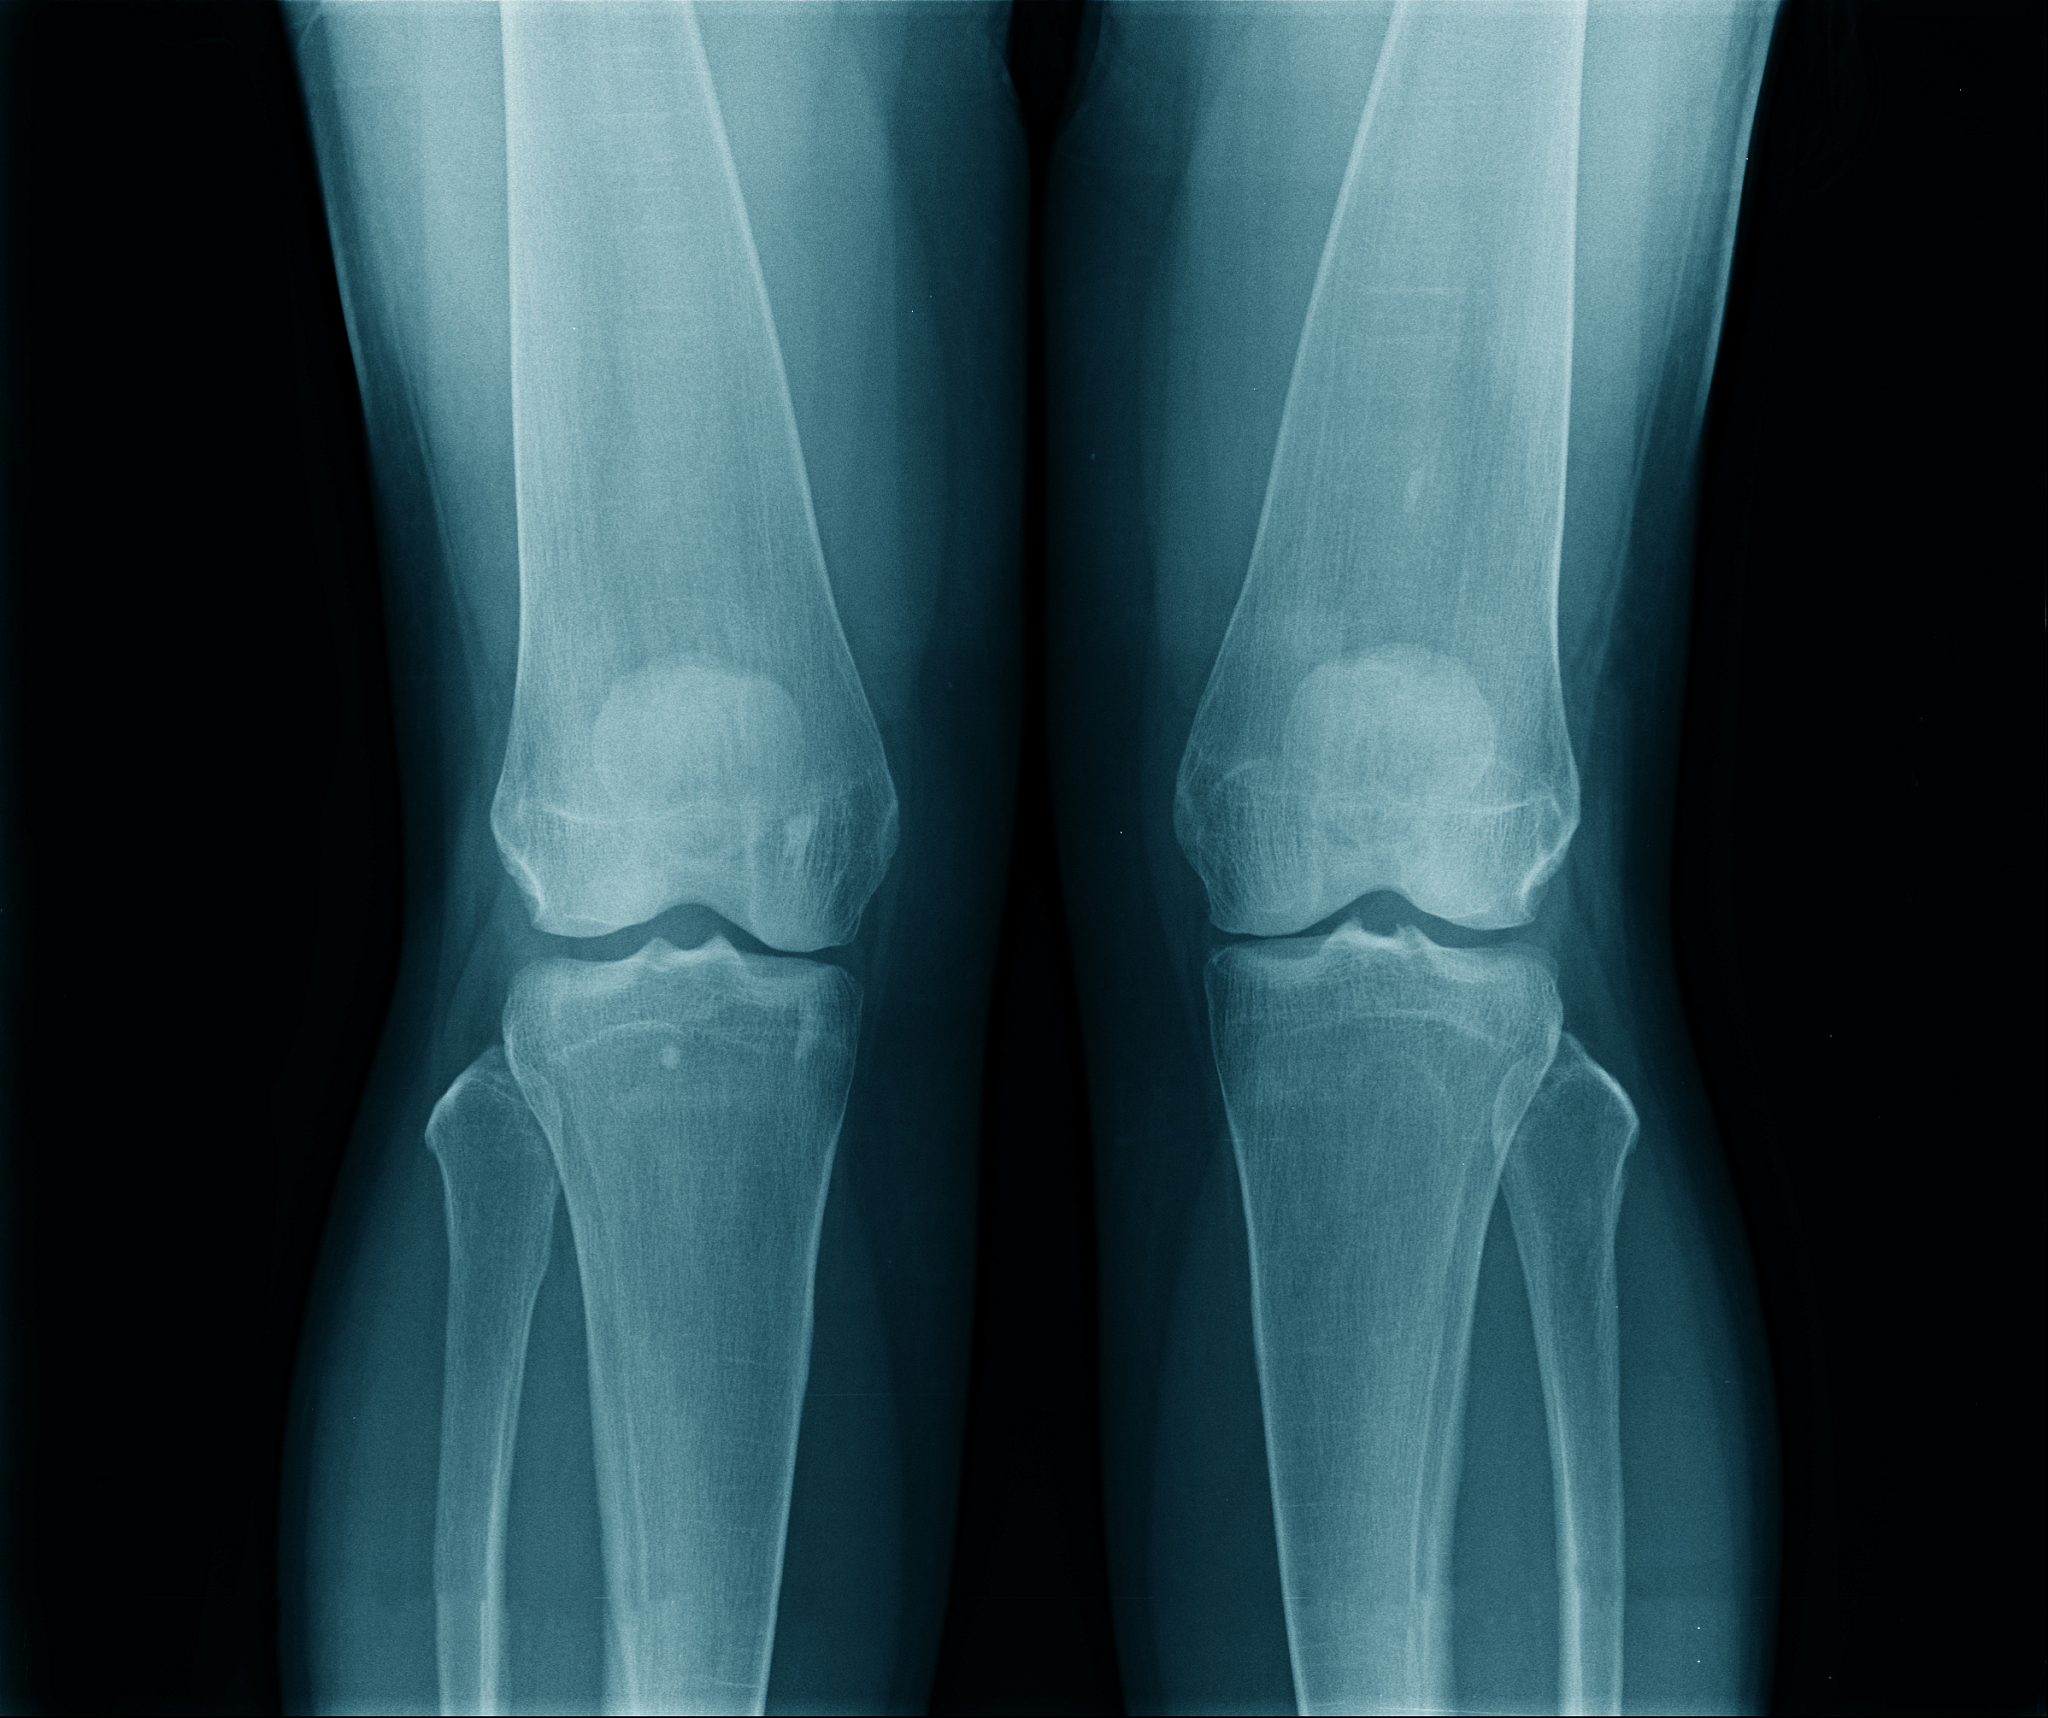

小腿骨连接大腿骨关节受伤有多痛?算轻伤吗?

打击小腿骨连接大腿骨的关节可能会引起剧痛,具体程度取决于打击的力度和个体的疼痛耐受能力。这种情况可能会造成关节软组织损伤、韧带扭伤、或者骨裂等伤害。是否算轻伤还需要考虑其他因素,例如是否有关节脱位、骨折或严重瘀伤等。建议及时就医进行专业的检查和治疗。